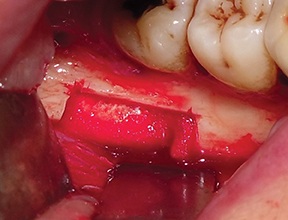

A full-thickness trapezoidal flap was elevated to expose the recipient site (Fig. 4). After releasing all muscular attachments, flap extension was checked coronally (Fig. 5).

Fig. 4: Intraoral view of the atrophic bone area

Block by Block

Fig. 5: Extent of flap release